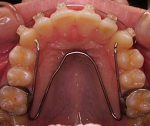

■側方からの力が持続的にかかっていると,通常で

あればU字型に発育するはずのアーチが,V字型や

台形の狭窄した歯列の形になってしまいます

。

↑狭い歯列アーチ(左:V字/右:台形). 拡大治療↑の例

■上顎のアーチが狭いと,下顎の前方への発育や機能はブロックされてしまい,噛む・食べる・話す,にも悪影響が出てきます.上下の歯の接触具合も悪いので,噛む効率の低下による,消化不良などの問題,容姿や姿勢,呼吸(気道)への影響も考えなければなりません.